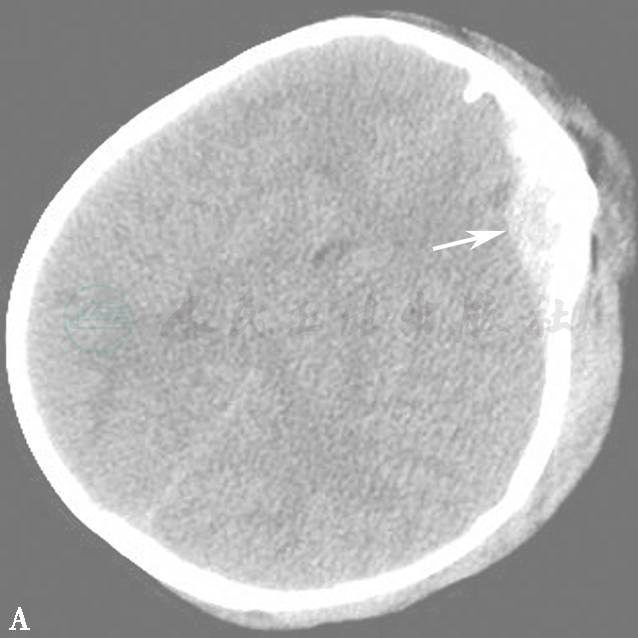

图15  外伤后颅内出血(箭)

A.脑组织窗;B.骨窗;C.VR重建